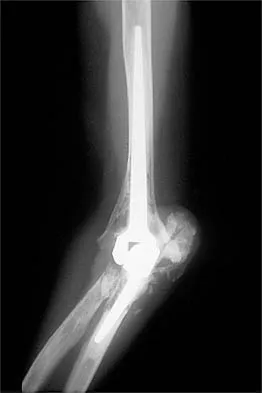

A 54-year-old woman sustained an elbow injury 3 months ago that was treated with open reduction and internal fixation. She now reports pain and limited elbow motion. Radiographs are shown in Figures 10a and 10b. Treatment should now consist of

Explanation

Radiographs reveal malunion of a Monteggia fracture-dislocation. Dislocation of the posterior radial head is caused by the malunited ulnar fracture. The deformity includes shortening with an apex posterior angulation. In the acute setting, open reduction of the radial head rarely is necessary; however, in chronic dislocations, open reduction is required. Without ulnar osteotomy, recurrent radial head dislocation is likely.